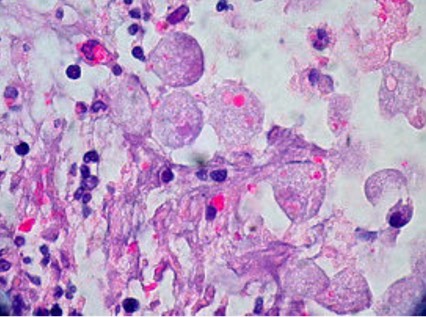

Deffinition of Amebiasis

A parasitic infection of the colon with the amoeba Entamoeba histolytica.